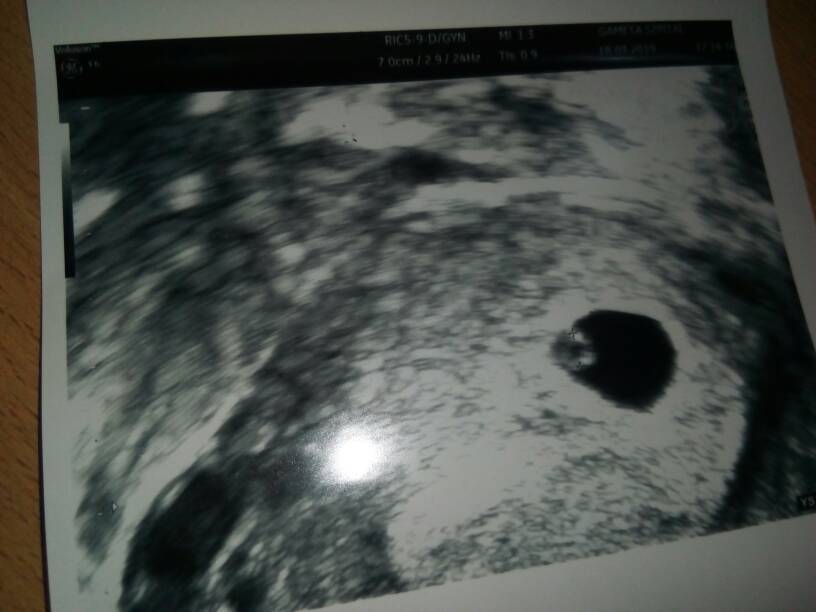

Super gratuluje!Wasze kciuki pomogły [emoji4] wczoraj wizyta 6+0, jest zarodek i to z serduszkiem [emoji175]

Wasze kciuki pomogły [emoji4] wczoraj wizyta 6+0, jest zarodek i to z serduszkiem [emoji175]